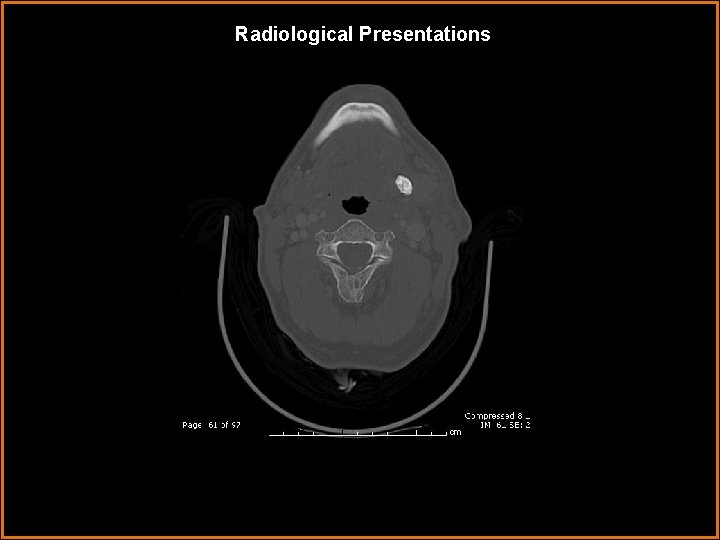

Radiological Presentations

Findings and Differentials Findings: Markedly enlarged, enhancing left submandibular gland with a large 1. 1 cm stone in Wharton’s duct. Differentials: • Submandibular venous vascular malformation – lobulated, heterogenously enhancing mass. • Sialosis – painless bilateral enlargement of salivary glands, usually the parotid glands. Associated with diabetes, obesity, and alcoholism. • Kuttner tumor – pseudomass of salivary gland associated with calcification.

Diagnosis Sialadenitis caused by sialolithiasis.